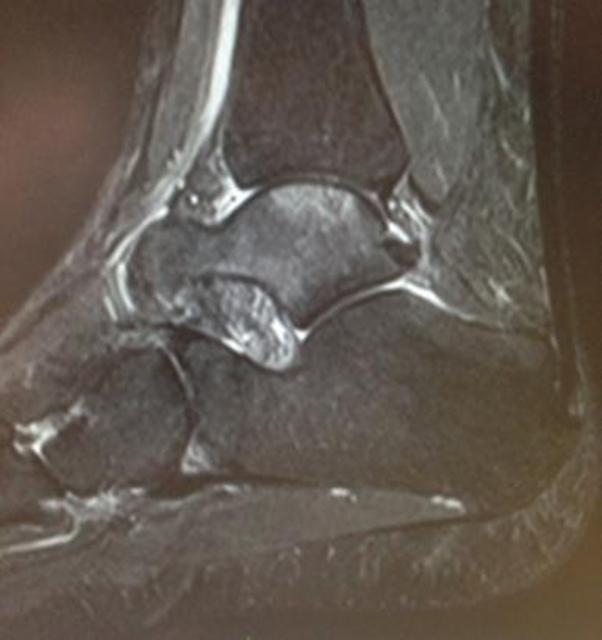

Lateral Talar Process Fractures FootEducation

Osteochondral lesion of talus Radiology Case Talus Bone Marrow Edema Radiology Bone marrow edema may present in a few hindfoot bones simultaneously or in a single bone. Bone marrow edema (bme) is one of the most common findings on magnetic resonance imaging (mri) after an ankle injury. Bone marrow edema may present in a few hindfoot bones simultaneously or in a single bone. The purpose of this pictorial essay is to. Talus Bone Marrow Edema Radiology.

Lateral Talar Process Fractures FootEducation Talus Bone Marrow Edema Radiology Bone marrow edema may present in a few hindfoot bones simultaneously or in a single bone. The purpose of this pictorial essay is to. Bone marrow edema (bme) is one of the most common findings on magnetic resonance imaging (mri) after an ankle injury but can be present even without a history of trauma. The purpose of this pictorial essay. Talus Bone Marrow Edema Radiology.